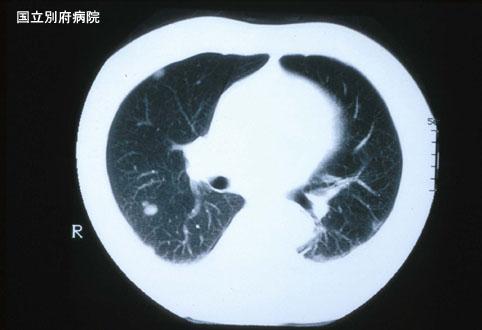

伴有肺转移的直肠恶性黑色素瘤(病例提供: 国立别府病院)

[ Image ID:3123 ]

疾病(病理主体)的分类

恶性黑色瘤/

部位(按器官分)

其他/

检查方法

CT